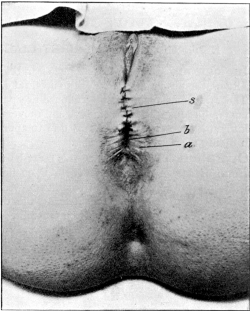

| 35. | Repair of a Lacerated Perineum, with Non-union of the Sphincter Ani, before a Plastic Operation | 133 |

| 36. | Repair of a Laceration of the Perineum after a Plastic Operation | 133 |